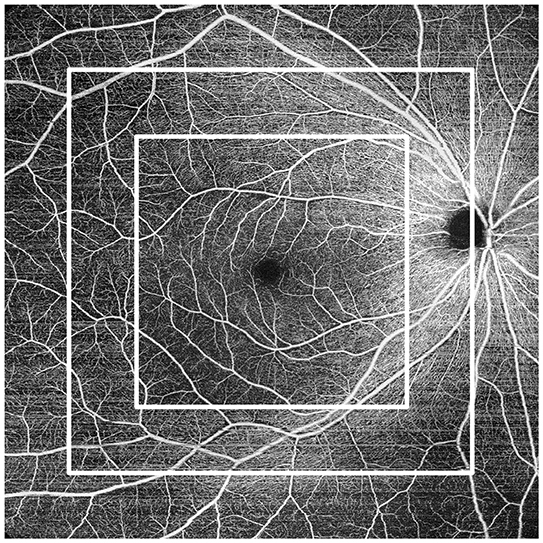

● Подобрена AngioScan OCT-ангиография, което допринася за по-широки и ясни изображения и улеснява диагностиката на хориоретиналната микроваскуалрна система